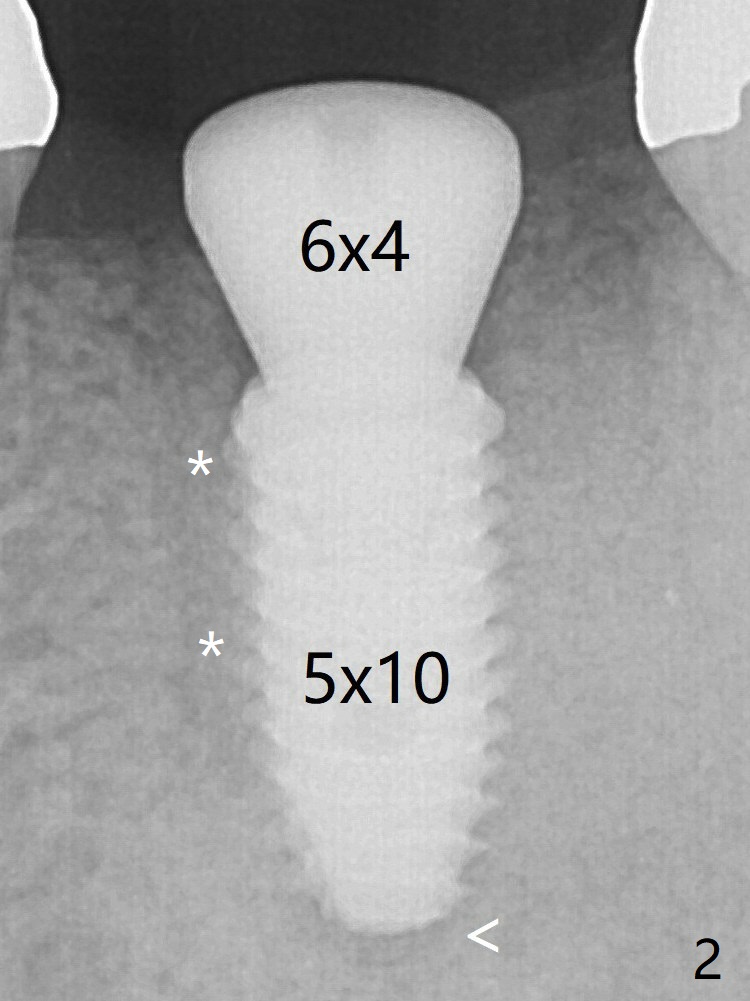

The bone is long enough to hold a 11.5 mm long implant. There is no difficulty in inserting the corresponding drill (4.5x11.5 mm) into the metal sleeve, but the lower right posterior teeth prevent the implant handpiece from going downward completely when the handpiece accesses lingually. Because of the extra manipulation, a 5x10 mm implant achieves insertion torque of ~ 20 Ncm (Fig.2). <: apical space. When the implant is placed initially according to the protocol/design, the implant is slightly supracrestal buccally. The implant is then seated apically ~.5 mm, which is unnecessary retrospectively. The bone density mesial to the implant (Fig2 *) increases 5 months postop (Fig.4), whereas that distal to the implant remains low 9 months postop (Fig.5). Bitewings taken 2.5 months post cementation (1 year postop, Fig.6,7) show subcrestal placement of the implant (advantage of guided surgery). The implant appears to be well protected; the crestal bone seems to cover the implant plateau (Fig.7 *). There will be little chance of thread exposure over years of use.